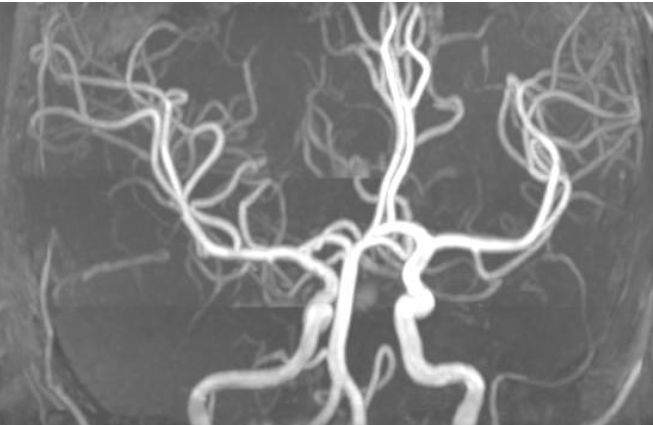

男患,12岁,发作性四肢无力,再发3天。主要表现:无明显诱因四肢无力,双下肢不能抬起,双上肢可抬起,但不能持物,持续约3小时后自行缓解,缓解期无不适。

答案: 静脉畸形(venous malformation),也称为脑发育性静脉畸形(cerebral developmental venous anomalies)

这个比较考眼力:DWI可见端倪, 箭头处为引流静脉。

不过这个疾病,上个星期刚刚学习过,所以大家比较熟悉,纷纷一针见血的猜中

脑发育性静脉畸形是最常见的脑血管畸形。常在CT、核磁检查时偶然发现。多数情况下为良性病程,个别情况下可伴临床症状,包括癫痫、局灶性神经功能障碍如运动感觉障碍、头痛、引起颅内出血相关症状等。可伴其他血管畸形,最常见的为海绵状血管瘤(12%-40%)。

典型征象:水母头征,由很多较细的髓静脉组成,这些髓静脉的血液汇入较粗的引流静脉。SWI和CT/MRI增强扫描尤为明显,其他核磁序列和CT平扫亦有可能显示。